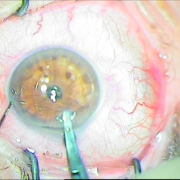

Μεταγχειριτική παρεκτόπιση ενδοφακού sun set syndrome

Μετεγχειριτική παρεκτόπιση ενδοφακού

Sun Set Syndrome

Συραφή του ίδιου φακού πίσω από την ίριδα

Συραφή του ίδιου φακού

πίσω από την ίριδα

Ευθυγραμμισμένος ενδοφακός